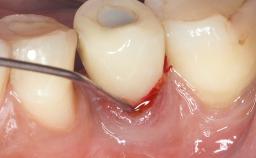

Despite anti-infective surgical treatment, some patients may experience recurrent infection and progressive bone loss requiring additional treatment. Removal of Implant Due to Recurrent Infection describes a conservative approach using an implant retrieval tool without the need for excessive bone removal or use of a trephine.

A 70-year-old female patient was referred by her general dentist to the periodontist for assessment and management of an infection associated with implant 36. The general dentist had noted suppuration on probing during examination.